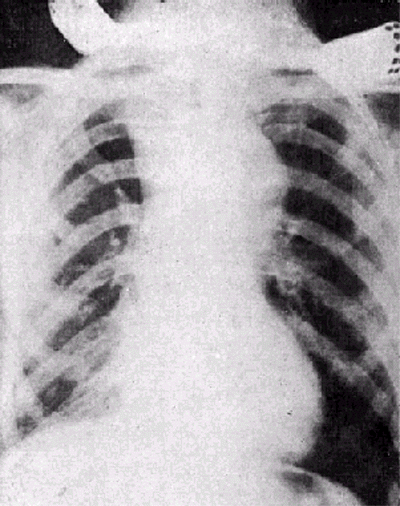

Рентгенография

Исследование аорты в прямой, левой передней косой и левой боковой проекциях позволяет диагностировать ее расширение, удлинение, отложения кальция в ее стенке, а также аневризматические выпячивания аорты.

Удлинение и расширение аорты чаще наблюдается при ее атеросклеротическом поражении и артериальных гипертензиях. При удлинении аорта выступает вправо и вверх и принимает участие в образовании правого верхнего контура сосудистой тени, значительно заходя на тень верхней полой вены. При этом верхний край аорты достигает уровня грудинно-ключичных сочленений (рис. 4.22). Кроме того, удлиненная аорта нередко образует изгибы, в связи с чем увеличивается верхняя дуга левого контура тени сердца (рис. 4.23).

| Рис. 4.23. Рентгенограмма сердца в прямой проекции больного с умеренным удлинением и расширением аорты. Тень аорты достигает уровня грудинно-ключичных сочленений, увеличена верхняя дуга левого контура тени сердца |

Расширение аорты приводит к общему увеличению поперечника ее тени и к еще большему выбуханию дуг аорты в правое и левое легочные поля. В левой передней косой проекции тень аорты становится развернутой, размеры аортального окна увеличиваются (рис. 4.24).